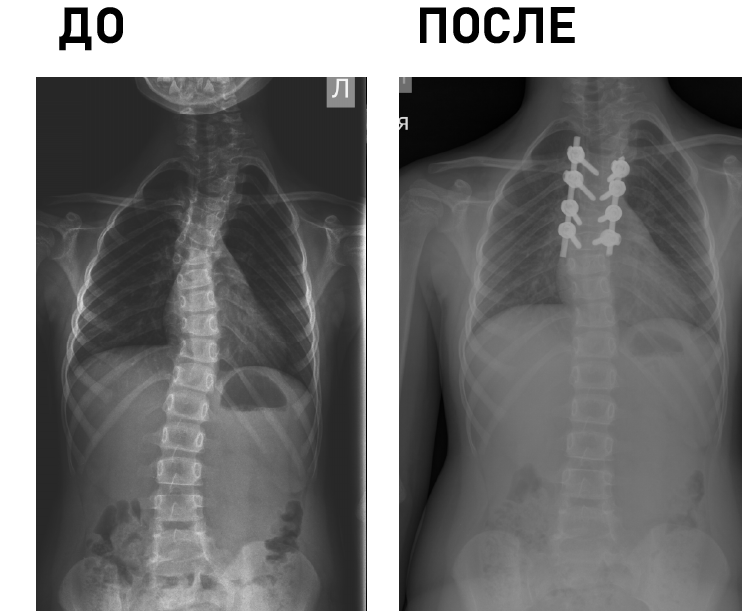

Технические возможности: технологии малоинвазивной (MIS) и реконструктивной хирургии, костнопластические материалы и инструментальная фиксация, современное силовое и ультразвуковое операционное оборудование, навигация, нейромониторинг.